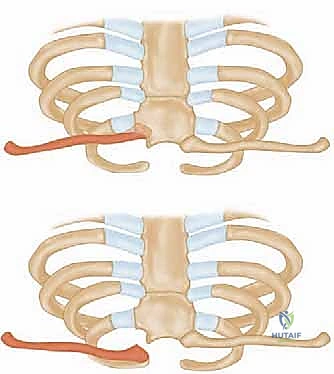

The epidemiological distribution of these injuries heavily favors anterior dislocations, with contemporary series reporting anterior-to-posterior dislocation ratios ranging from 3:1 to as high as 20:1. The mechanism of injury dictates the direction of displacement. Anterior dislocations typically result from an indirect force—specifically, a lateral compressive force applied to the shoulder girdle while the shoulder is rolled backward in extension. Conversely, posterior dislocations result either from a direct, high-energy blow to the anteromedial clavicle, or an indirect lateral compressive force applied while the shoulder is rolled forward in flexion. While anterior dislocations present a prominent, often cosmetically displeasing deformity, they are rarely life-threatening and can frequently be managed with non-operative, symptomatic care.

Acute posterior dislocations, conversely, demand immediate attention. Closed reduction should be attempted urgently, ideally within the first 48 hours, in a controlled environment such as the operating room with general anesthesia and cardiothoracic surgery available on immediate standby. The classic reduction maneuver involves placing a bump between the patient's scapulae, applying lateral traction to the abducted and extended arm, and utilizing a sterile towel clip to physically grasp the medial clavicle and lift it anteriorly. If closed reduction is successful, the joint is often stable, and non-operative management in a figure-of-eight harness or sling is appropriate. Operative intervention is strictly indicated when an acute posterior dislocation is irreducible by closed means, when it is highly unstable post-reduction, or when there are progressive signs of mediastinal compression (vascular compromise, dyspnea, dysphagia) that do not resolve with reduction attempts.

Once the joint is exposed, the pathology is assessed. In an acute setting, the torn remnants of the anterior and posterior capsule are identified and tagged with heavy non-absorbable sutures. If the intra-articular disc is irreparably torn or blocking reduction, it may be excised, though preserving it is preferable if possible. Reduction of the joint is then performed under direct visualization. For a posterior dislocation, a bone hook or a robust towel clip is placed around the medial clavicle to pull it anteriorly and laterally, while an assistant applies lateral traction to the abducted arm.